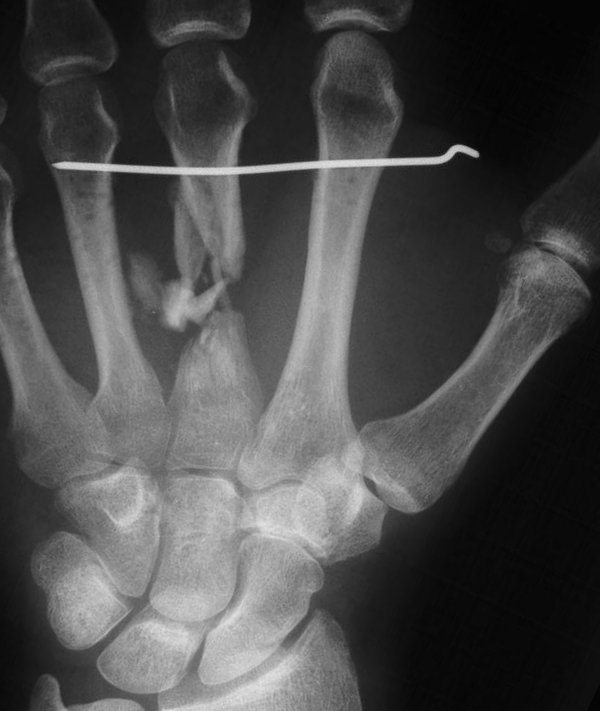

The injury: point blank handgun injury, palmar to dorsal through the middle metacarpal. Contusion of the third web space common digital nerve.

The treating surgeon debrided the wound and maintained length with intermetacarpal pins. When the wound was stable, the fracture was treated with bone graft, plate and screws.